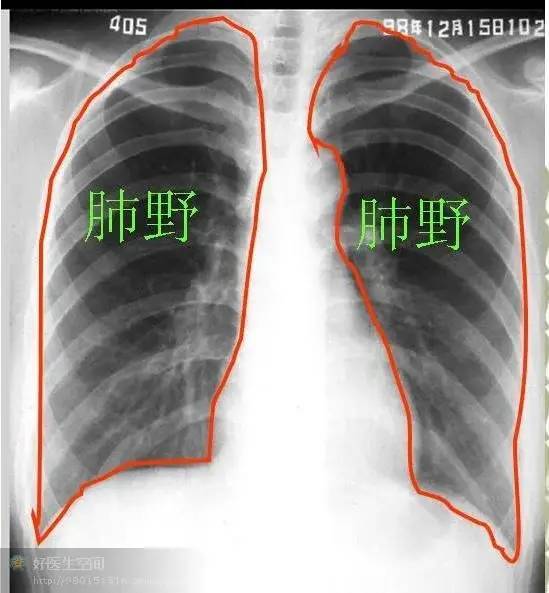

肺部疾病影像学阅片 一,正常胸片 正常胸片(正位片)